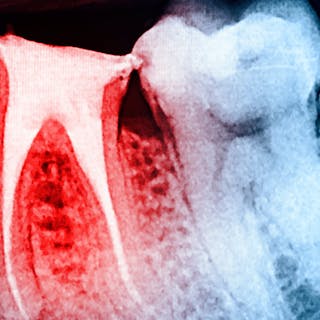

In another example, a young patient had been using e-cigarettes for five years. He started vaping as a method to quit smoking traditional tobacco products thinking vaping was a healthy alternative. Because of its ease of use, he smoked a cartridge of one of the more popular vaping products a day. Admittedly, he also drank energy drinks (high sugar content), stating that his mouth was often dry after vaping. This combination led to rampant decay with smooth-surface lesions and future tooth loss (figure 3).

Figure 3: Effects of e-cigarettes